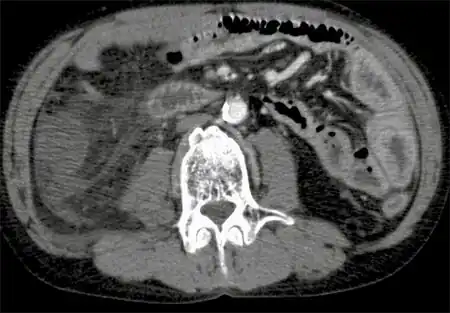

P. shigelloides has been isolated from a wide variety of human clinical specimens including both intestinal (usually feces or rectal swabs) and extra-intestinal. It has been isolated from the feces of humans, both with and without diarrhea, and/or vomiting (gastroenteritis). Although reports have found a link between P. shigelloides and diarrhea or gastroenteritis, research has not yet determined whether this bacteria is always responsible for these conditions.[4]